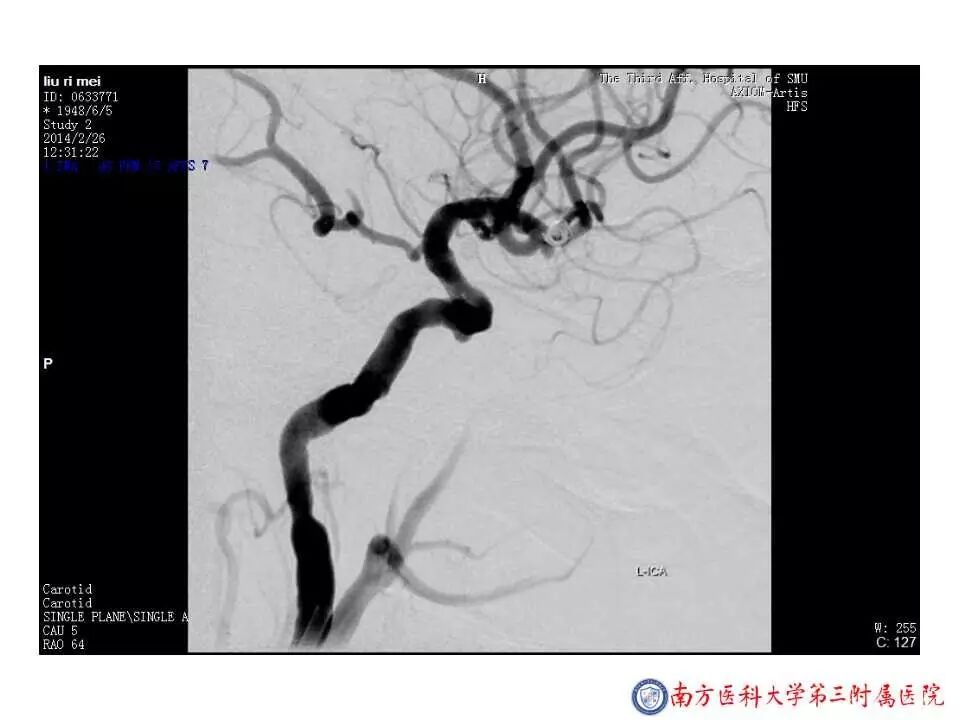

今天为大家分享的是“强生医疗CNV-神经介入专栏”第二十五期,由南方医科大学第三附属医院神经外科主任黄理金教授带来的“Enterprise支架辅助栓塞动脉瘤的优势”精彩讲课视频及PPT,欢迎观看。文章仅代表作者个人观点,如有不同见解,欢迎同道斧正!